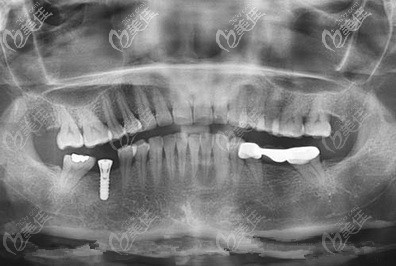

而院內(nèi)做的種植體品牌則有:韓國(guó)登騰、奧齒泰、美國(guó)皓圣、瑞士ITI等種植品牌。

不僅如此,青島牙博士口腔還擁有Fotona水激光、3shape掃描儀、塊錢數(shù)字化CBCT機(jī)等先進(jìn)的設(shè)備。